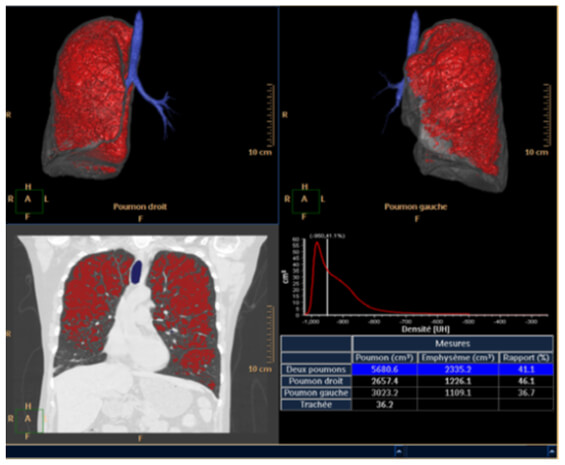

Emphysema Measurement

The automated application called “lung density” provides the physician with quantitative data on the volume of pulmonary emphysema, as well as gives us a visual representation of its diffusion.